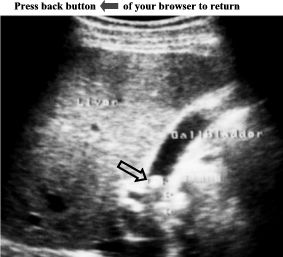

Ultrasound

examination

of

gallbladder

showed

an

asymmetric

thickening

the

wall

(7mm)

with

a

single

central

hypoechoic

zone

sandwiched

two

echogenic

layers,

see

white

arrows. An

hyperechoic,

round

mass

posterior

acoustic

shadow

was

demonstrated

impacted

in

neck

(see

black

arrow).

No

pericholecystic

fluid

collection

present.